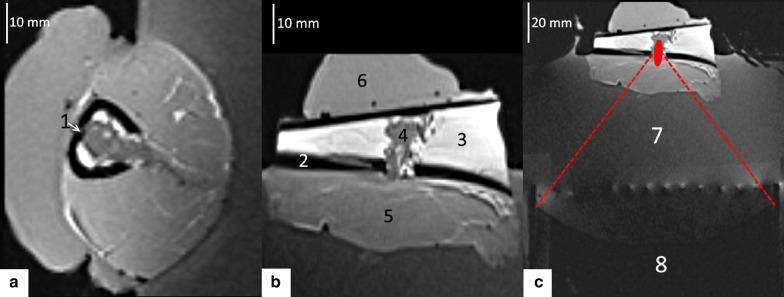

Experiments were conducted on ex vivo lamb shank by mimicking osteolytic bone tumours. The cortical breakthrough was exploited to induce hyperthermia inside the medullar cavity by delivering acoustic energy from a phased array HIFU transducer. MR thermometry data was acquired intra-operatory using the proton resonance frequency shift (PRFS) method. Active temperature control was achieved via a closed-loop predictive controller set at 6 °C above the baseline. Several beam geometries with respect to the cortical breakthrough were investigated. Numerical simulations were used to further explain the observed phenomena. Thermal safety of bone heating was assessed by cross-correlating MR thermometry data with the measurements from a fluoroptic temperature sensor inserted in the cortical bone.

Numerical simulations and MR thermometry confirmed the feasibility of spatio-temporal uniform hyperthermia (± 0.5 °C) inside the medullar cavity using a fixed focal point sonication. This result was obtained by the combination of several factors: an optimal positioning of the focal spot in the plane of the cortical breakthrough, the direct absorption of the HIFU beam at the focal spot, the "acoustic oven effect" yielded by the beam interaction with the bone, and a predictive temperature controller. The fluoroptical sensor data revealed no heating risks for the bone and adjacent tissues and were in good agreement with the PRFS thermometry from measurable voxels adjacent to the periosteum.